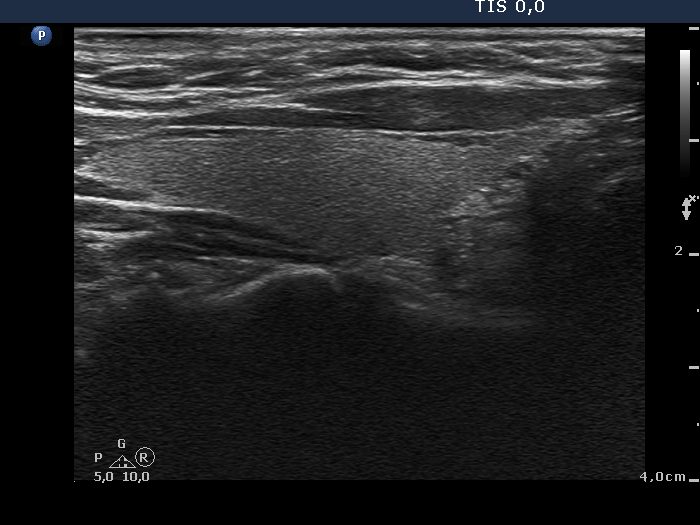

Intranodular hyperechogenic figures - case 1091

Follow-up examination one year later (ultrasonographic picture 2)

Right lobe, longitudinal view.